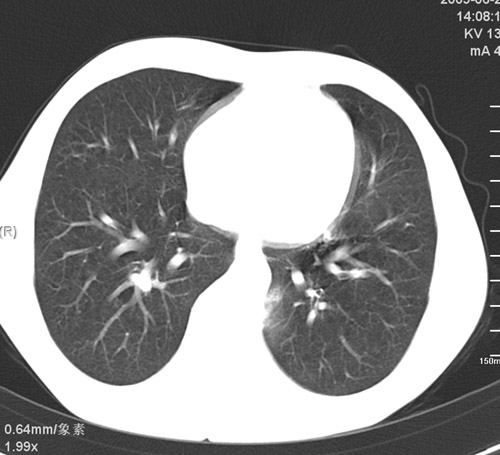

以下是引用513ytb在2009-7-1 14:34:00的发言:[br]考虑肺囊肿伴感染可能性大。外伤性肺气囊肿。

以下是引用光影★小胖在2009-7-1 15:05:00的发言:[br]外伤所致液气囊肿。

以下是引用zjzjr在2009-7-1 17:00:00的发言:[br]外伤所致液气囊肿。小的支气管损伤引起.